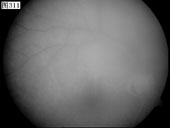

[组图]优秀眼底图片奖网上评选活动启动         ★★★

优秀眼底图片奖网上评选活动启动

优秀眼底图片奖应征作品展示